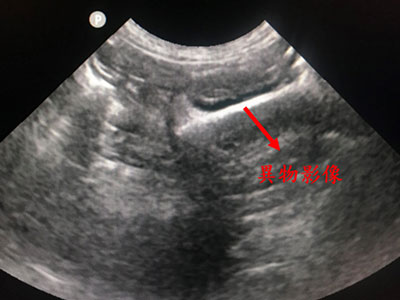

X光及腹腔超音波檢查在小腸段發現了一條高阻塞度的異物影像,疑似為骨頭且尖端銳利。